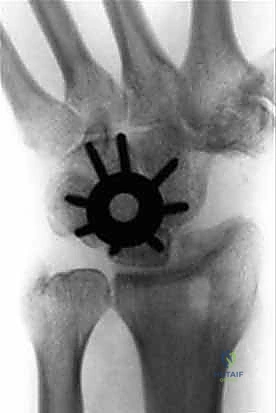

1. دمج الزوايا الأربع (Four-Corner Fusion)

هي العملية الأكثر شيوعاً وشهرة في حالات الانهيار المتقدم (SLAC/SNAC).

* الآلية: يتم استئصال "العظم الزورقي" (Scaphoid) بالكامل لأنه يكون غالباً مصدر المشكلة والألم. بعد ذلك، يتم دمج العظام الأربعة المتبقية في المركز معاً: العظم الهلالي (Lunate)، العظم الكبير (Capitate)، العظم الكلابي (Hamate)، والعظم المثلثي (Triquetrum).

* النتيجة: يتم نقل الحمل الميكانيكي للرسغ من الجانب الزورقي المريض إلى الجانب الهلالي السليم، مما يلغي الألم مع الحفاظ على حركة جيدة للرسغ من خلال المفصل الكعبري الهلالي (Radiolunate joint).